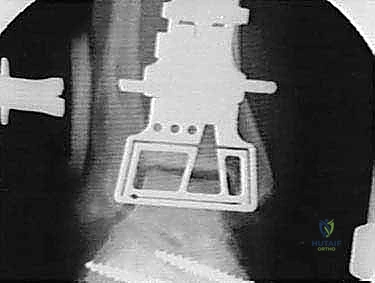

يتميز نظام Agility Total Ankle System بتصميم فريد من نوعه يختلف عن المفاصل الصناعية الأخرى. يعتمد هذا النظام على مبدأ الميكانيكا الحيوية المتقدمة، حيث يتكون من مكونين رئيسيين:

1. مكون ظنبوبي (Tibial Component): قطعة معدنية تُثبت في عظمة الساق (القصبة). الميزة العبقرية لنظام Agility هي أنه يتطلب دمج المفصل الظنبوبي الشظوي السفلي (Tibiofibular syndesmosis). هذا يعني أن الجراح يقوم بدمج عظمة القصبة مع عظمة الشظية لإنشاء قاعدة عريضة وقوية جداً تدعم المفصل الصناعي وتمنع ارتخاءه بمرور الوقت.

2. مكون كاحلي (Talar Component): قطعة معدنية تُثبت في عظمة الكاحل، مع وجود سطح بلاستيكي عالي الكثافة (البولي إيثيلين) بين المكونين لضمان انزلاق سلس وحركة طبيعية.

هذا التصميم الواسع يوفر استقراراً دورانياً فائقاً، ويقلل من الضغط المتركز على نقطة واحدة، مما يزيد من العمر الافتراضي للمفصل الصناعي.

5. زراعة المفصل الصناعي (Implantation)

يتم إدخال المكون الظنبوبي (العلوي) والمكون الكاحلي (السفلي) وتثبيتهما بإحكام. يتم إدخال القطعة البلاستيكية (البولي إيثيلين) بينهما. يقوم الدكتور هطيف باختبار حركة المفصل وتوازنه وشد الأربطة لضمان استقرار المفصل في جميع الاتجاهات.